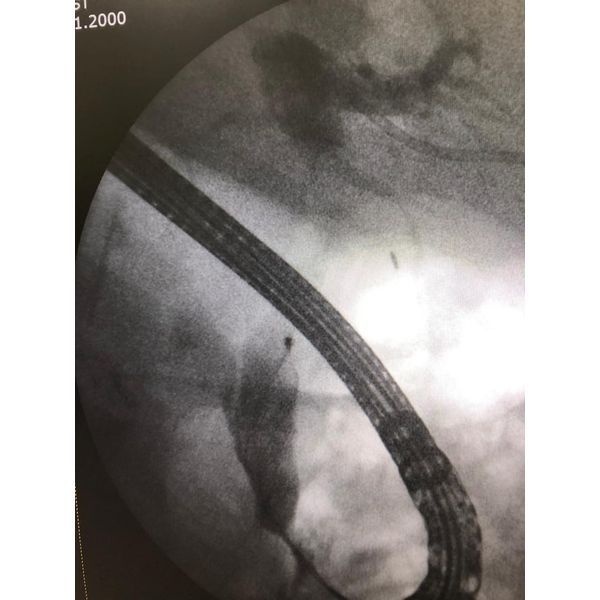

- ретроградную панкреатохолангиографию — комплексное исследование желчных протоков и протоков поджелудочной железы с помощью эндоскопа;

- папиллотомию — расширение выходного отверстия Фатерова сосочка для улучшения оттока желчи из общего желчного протока;

- холедохолитоэкстракцию — извлечение камней.

Однако извлечь крупные камни из общего желчного протока не удалось, поэтому через месяц пациент прошёл ещё одну операцию — наноимпульсное дробление камней (холедохолитотрипсию) с помощью аппарата SpyGlass.